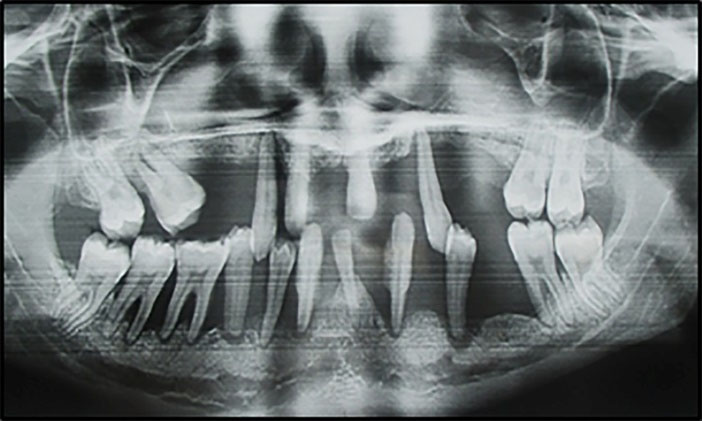

The significant variables selected for analysis by logistic regression, shown in Table 3, were: variables not related to periodontal status: age, socioeconomic status, smoking habits, brushing frequency and variables related to periodontal status: teeth lost and mobile teeth. Having at least 5 mobile teeth (OR= 4.11, 95% CI: 2.95‒5.73, P=0.000), and/or 5 missing teeth (OR=2.60, 95% CI: 1.85‒3.66, P=0.000) were identified as independent risk indicators for severe periodontitis (Figures 2 and 3).

japid-14-7-g002

Figure 2. Clinical front view of generalized severe periodontitis (Stage IV / Grade C) of a 18 year patient. Note the presence of attachment loss, dental migration/mobility, and missing teeth: destruction exceeds expectation given biofilm deposits.

Figure 3. A panoramic X-ray of the patient presented in figure 1. Note severe generalized radiographic bone loss extending to the apical third of the root: % bone loss/age (100% / 18 = 5.5) > 1.0